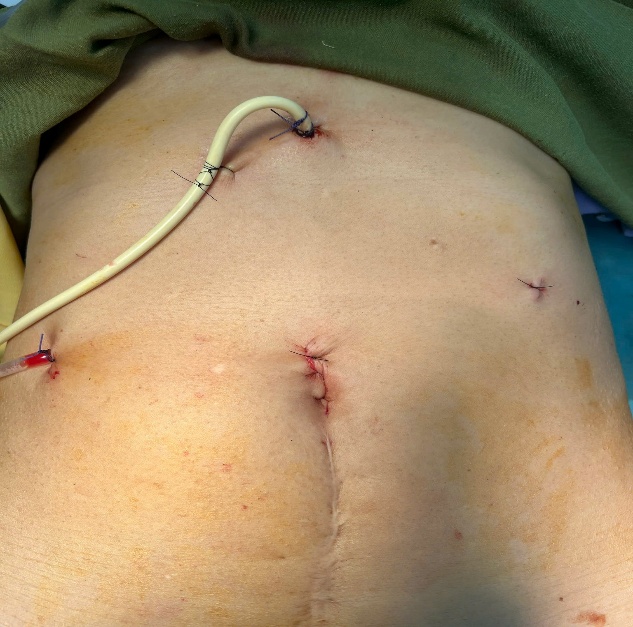

Bệnh nhân nữ 67 tuổi xuất hiện đau hạ sườn phải từng đợt nhiều năm, Mỗi lần đau thường kèm theo sốt, vàng da. BN đã đi khám ở tuyến trên được chẩn đoán tắc mật do sỏi ống mật chủ và sỏi trên gan. BN được chỉ phẫu thuật và quyết định mổ tại BVĐK Hải Dương. Chúng tôi sau khi xem xét hồ sơ bệnh án đã quyết định thực hiện phẫu thuật nội soi tán sỏi OMC và sỏi trên gan kèm tán sỏi Laser. Ca mổ đã diễn ra vô cùng thuận lợi. Sau 2 tiếng ca mổ đã hoàn thành. Sỏi trên gan và sỏi OMC được tán nhỏ và lấy qua nội soi. Sau 10 ngày điều trị hậu phẫu bệnh nhân đã được ra viện.

Hình ảnh sỏi và BN sau mổ với vết mổ rất nhỏ

Bn nữ 44 tuổi đau thượng vị nhiều đợt. Đi khám và được chẩn đoán xơ teo thùy gan trái do sỏi gan trái. Sau hội chẩn được chỉ định cắt thùy gan trái nội soi. Trong ca mổ chung tôi đã sử dụng dao hàn mạch Ligasure và Stapler để tiến hành cắt gan trái cho bệnh nhân. Ca mổ đã diễn ra thuận lợi không chảy máu. BN ra viện sau 7 ngày.

Hình ảnh sỏi và phần gan được cắt bỏ qua nội soi.